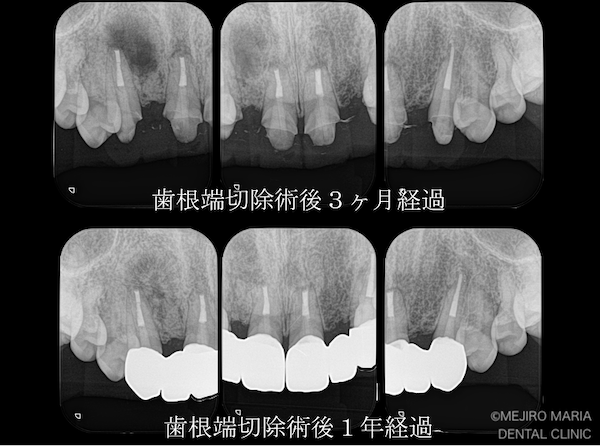

精密根管治療(歯内療法)終了後1年が経過し、レントゲンでも根尖性歯周炎の治癒が確認できました。病変が大きいため、レントゲン上の治癒像は特徴的ですが、硬組織(歯や骨)の治癒は良好と判断できます。

歯肉の状態も、術後3ヶ月では切開線の瘢痕が若干確認できたものの、1年後の経過観察では上顎前歯部にはほぼ見られず、非常に良好であると判断できます。